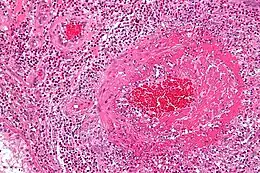

Coupe histologique d'une vascularite éosinophilique liée à un syndrome de Churg-Strauss (coloration à l'hématoxyline et à l'éosine)

La granulomatose éosinophilique avec polyangéite est une vascularite nécrosante qui touche les artères et les veines de petit calibre avec lésions. C’est-à-dire que l’inflammation des vaisseaux entraîne l’épaississement et la fragilisation des parois. À l’inverse, une sténose peut se créer (rétrécissement des vaisseaux). Le flux sanguin en est donc perturbé, celui-ci ayant du mal à passer en quantité suffisante. Différents organes sont alors en ischémie (arrêt de passage du sang ). Cela peut être temporaire ou définitif, selon l’état de gravité du système atteint[6].

Comme souligné précédemment, différents organes peuvent aussi comporter un surnombre de polynucléaires éosinophiles. Ces globules blancs se rassemblent en granulomes et provoquent ainsi une réaction inflammatoire anormale. Les granulomes extravasculaires sont très caractéristiques de l’angéite (inflammation) de Churg et Strauss, mais ne sont ni constants, ni pathognomoniques.

Des biopsies peuvent être faites au niveau de la peau, des muscles, des reins ou des poumons. L’observation au microscope montrera la présence de vascularite systémique et/ou d’éosinophiles en dehors des vaisseaux. Une inflammation des reins peut également être vue (glomérulonéphrite).